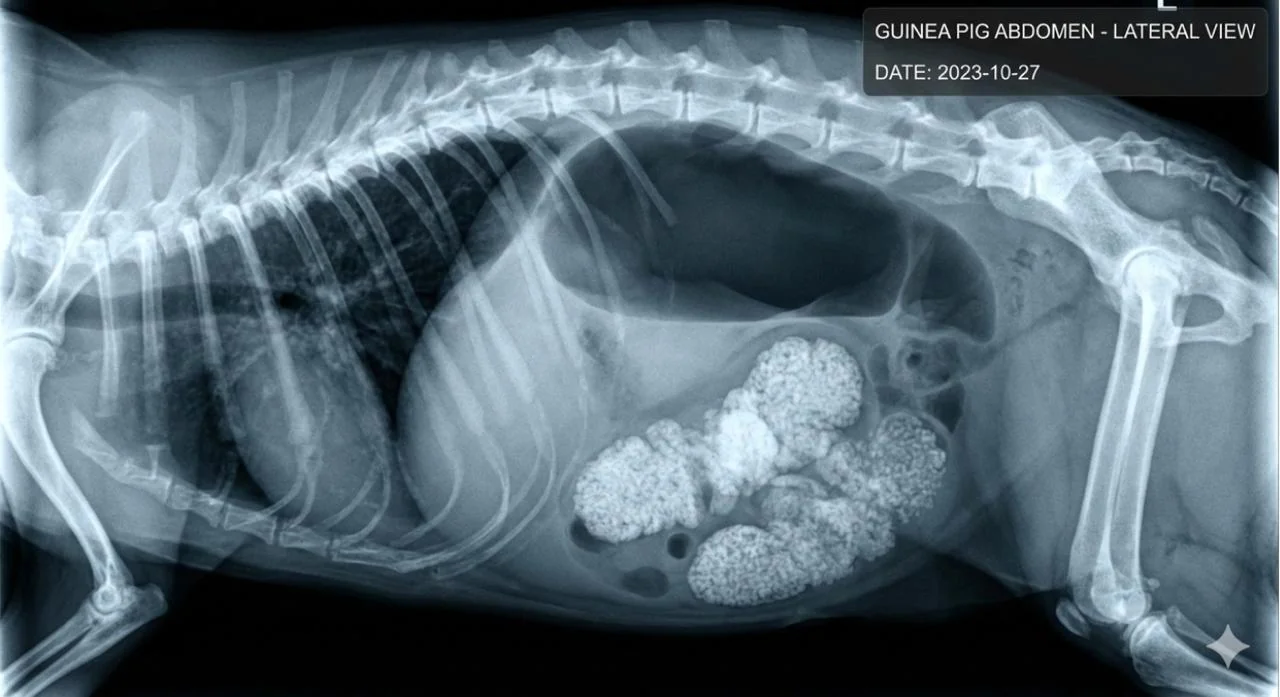

Шлунково-кишковий стаз у кролів та гризунів є невідкладним станом, який вимагає негайного втручання фахівця-ратолога. Фізіологія цих тварин налаштована на постійний пасаж грубих рослинних волокон, і будь-яка затримка перистальтики призводить до небезпечного накопичення газів та токсинів. В АртВет ми розглядаємо стаз не як окрему хворобу, а як наслідок системного дискомфорту: причиною може стати стрес, дентальні проблеми або незбалансований раціон. Голодування протягом декількох годин запускає процес ліпідозу печінки, що значно ускладнює прогноз та лікування.

Клінічна стратегія АртВет у таких випадках спрямована на швидке відновлення гідратації та стимуляцію моторики. Ми проводимо детальну діагностику, включаючи рентгенографію, щоб виключити повну механічну обструкцію, яка вимагає хірургічного втручання. Важливим аспектом опіки є забезпечення адекватної анальгезії, оскільки біль від розтягнення стінок кишечника є головним чинником, що перешкоджає відновленню апетиту. Розуміння цих механізмів дозволяє нам ефективно стабілізувати пацієнтів навіть у важкому стані та запобігати рецидивам через корекцію умов утримання.